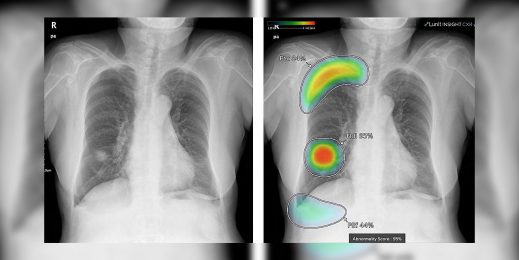

(Изображение: Lunit)